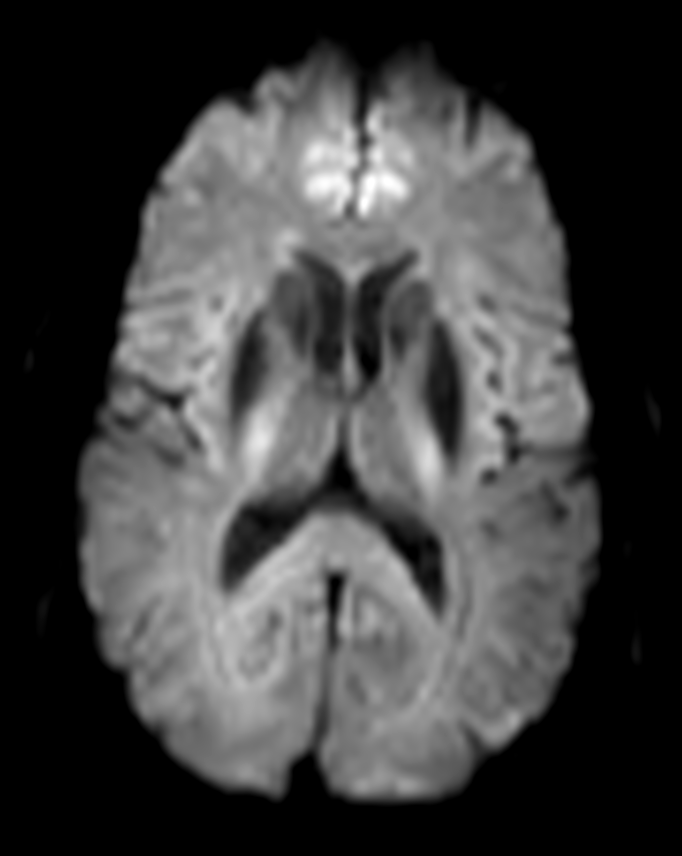

Axial DWI b1000